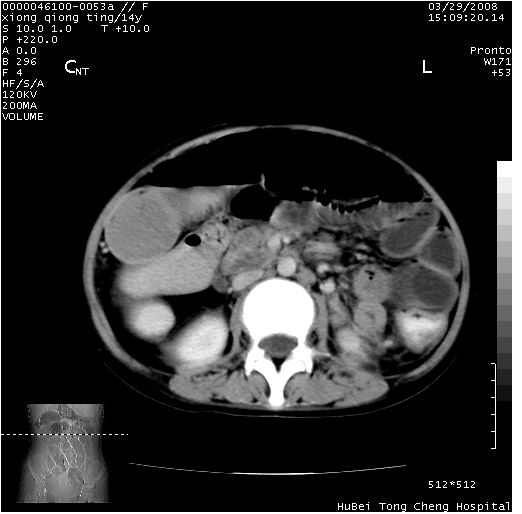

患儿 女,14岁。不规则发热一周,偶感头痛,无抽搐及呕吐。pe:神清,精神差,双侧瞳孔等大等圆,对光反射敏感,双肺未闻及明显啰音,心音有力,腹部触之似揉面感,下腹压痛,无反跳痛。

腹部b超提示:子宫缩小,盆腔积液,肝实质回声密集。

临床诊断:发热原因待查:1)腹部结核感染。2)伤寒?3)结缔组织病?

中下腹及盆腔ct轴位平扫+增强扫描(层厚10mm,螺距1.0,重建间隔10mm),图像如下:

(注:患儿检查当日上午9时口服胃肠道对比剂,下午3时许行ct扫描检查,未行对比剂直肠保留灌肠,检查当日患儿腹泻)

中下腹及盆腔ct轴位扫描(ps+ce)提示:腹部肠管明显充气扩张,并见数个不同宽度之气液平面;疑不全性肠梗阻或肠郁张。临床会诊考虑为患儿腹泻,肠郁张所致;后来未经特殊处理,患儿大便恢复正常,亦无腹胀。

临床出院诊断:1)结核性腹膜炎。2)腹膜后淋巴结结核。3)脂肪肝。